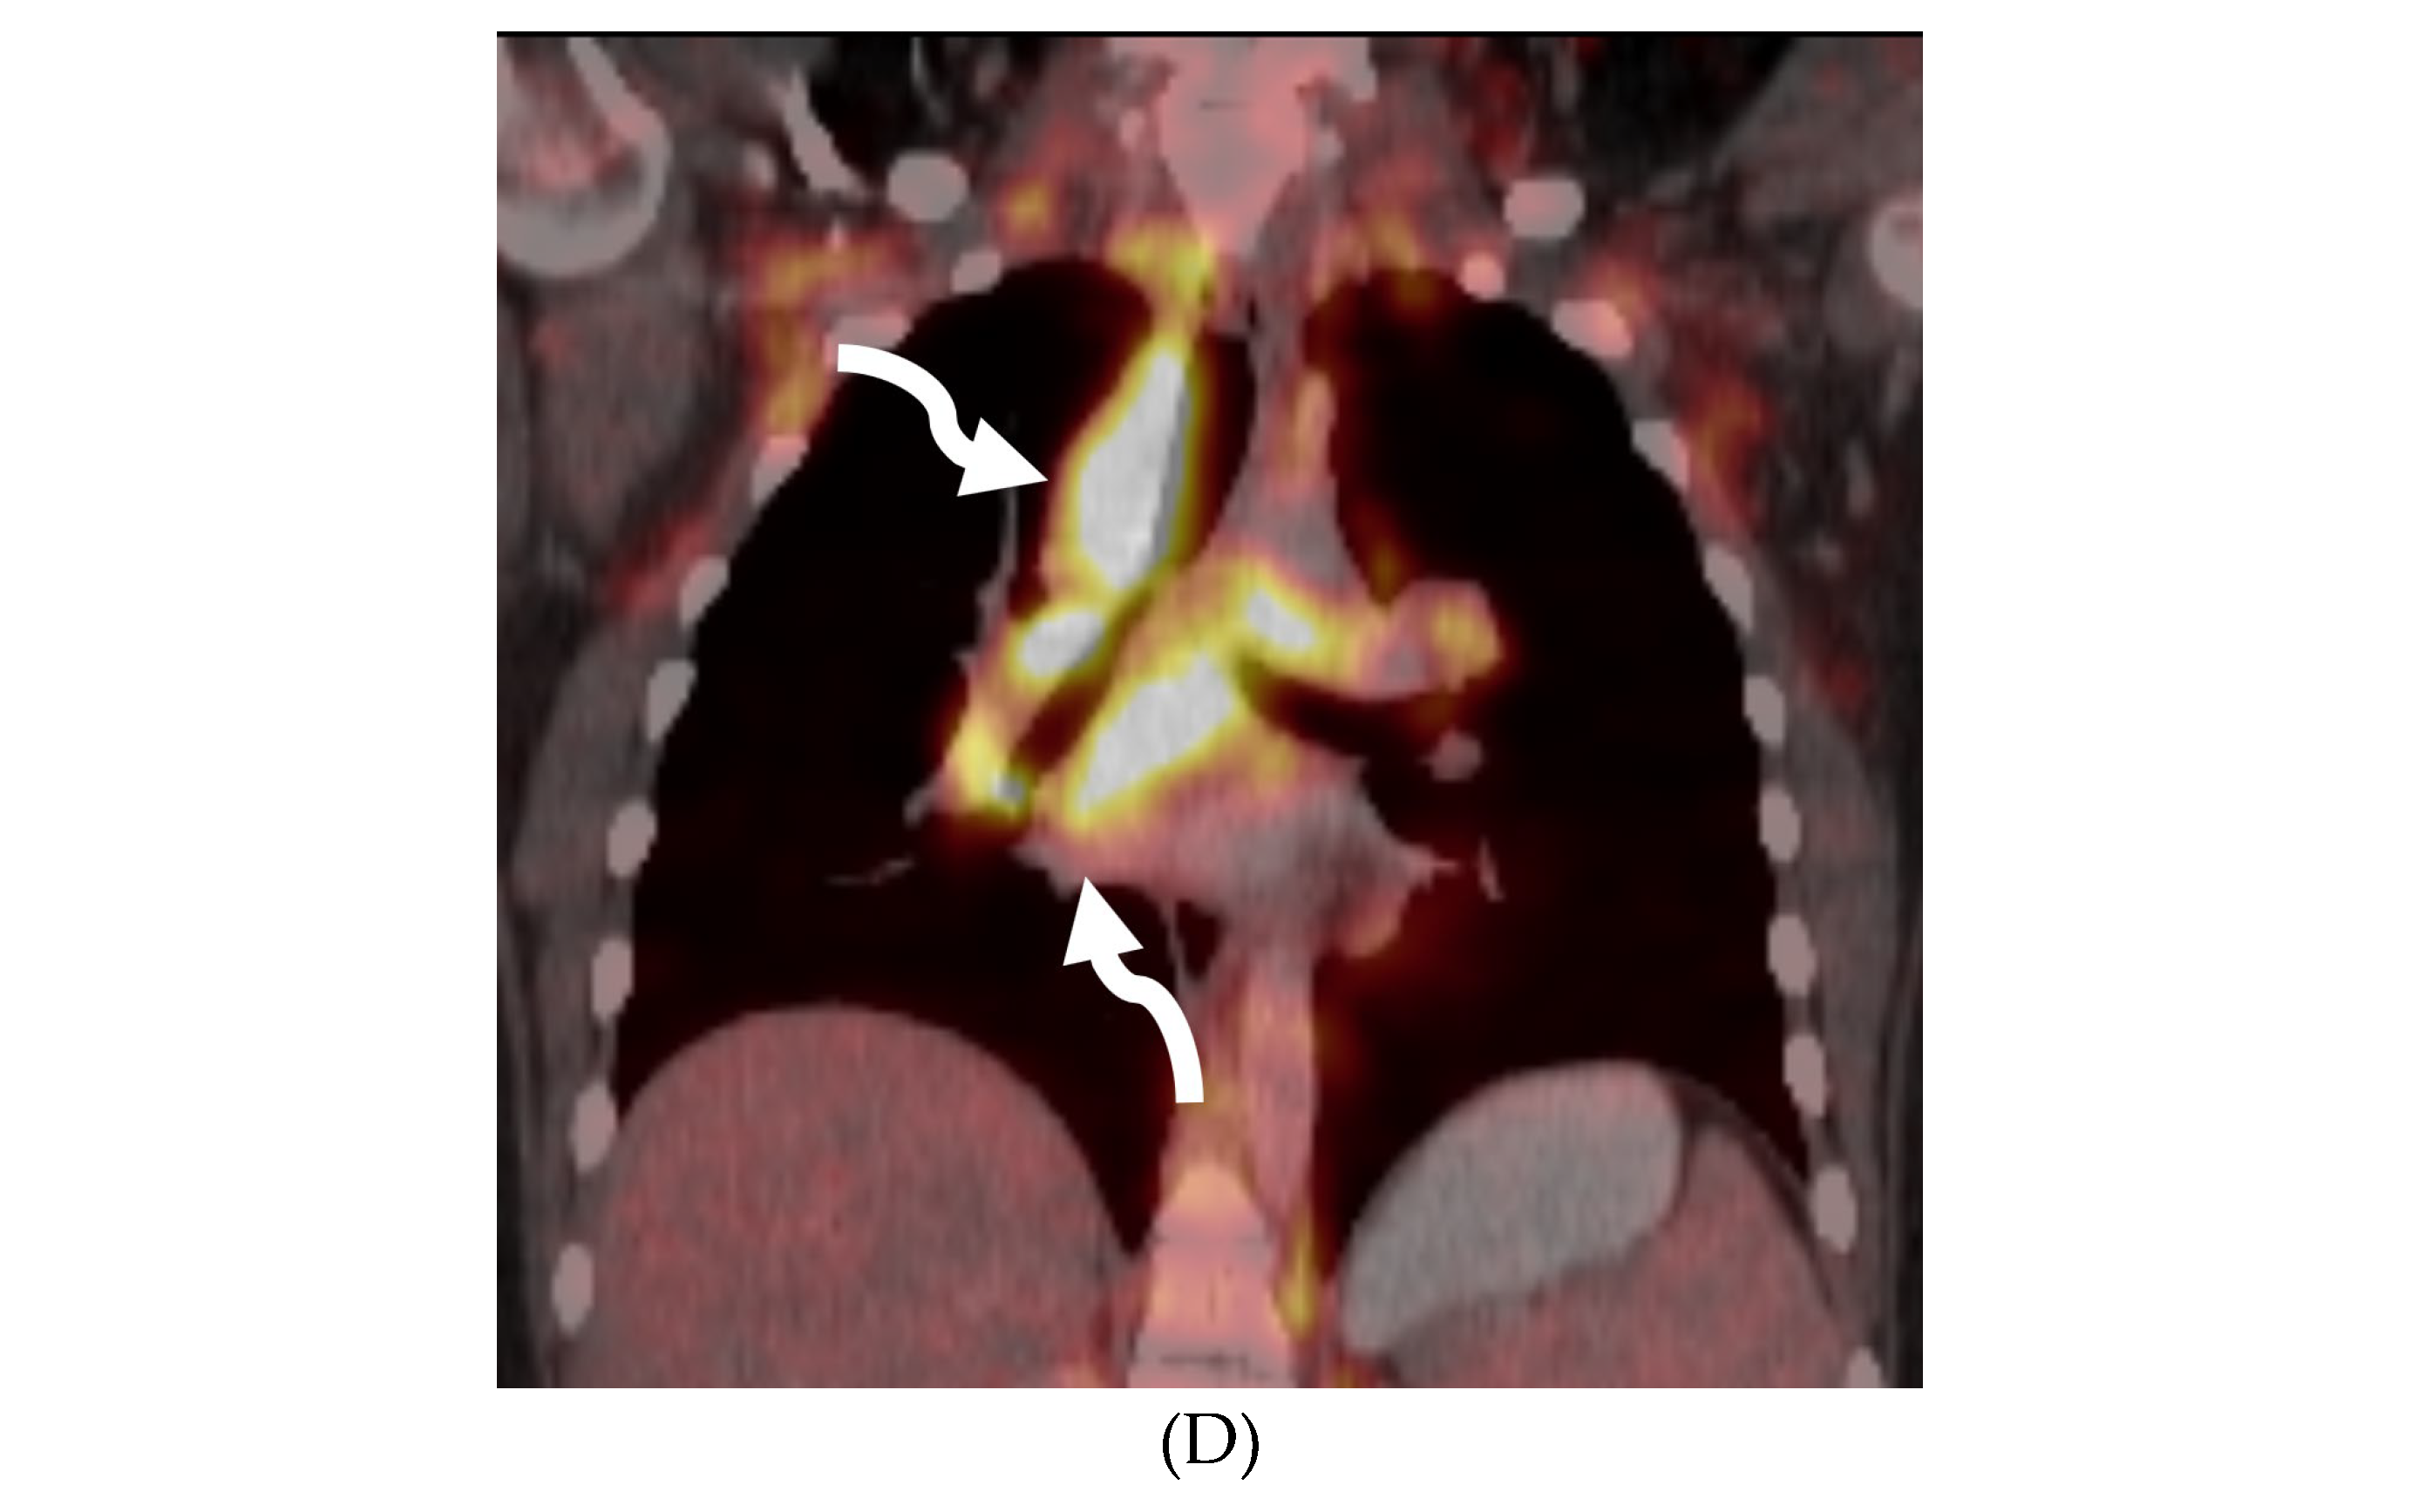

SYSTEMIC MENINGEAL METASTASES (SMM)

MOYA MOYA